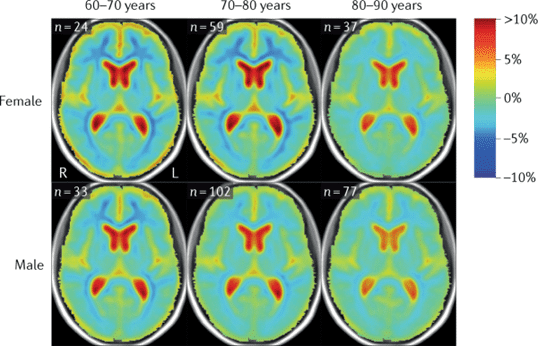

Brain atrophy in women and men with amnestic mild cognitive impairment

Men and women with Alzheimer disease experience different cognitive and psychiatric symptoms. Women undergo faster cognitive decline after diagnoses with mild cognitive impairment or dementia.

Brain atrophy rates and patterns differ between genders along the disease continuum; in mild cognitive impairment, brain atrophy is more rapid in women than in men.

Men and women have differing prevalence and impact of metabolic, cerebrovascular, and socioeconomic risk factors for Alzheimer’s disease.